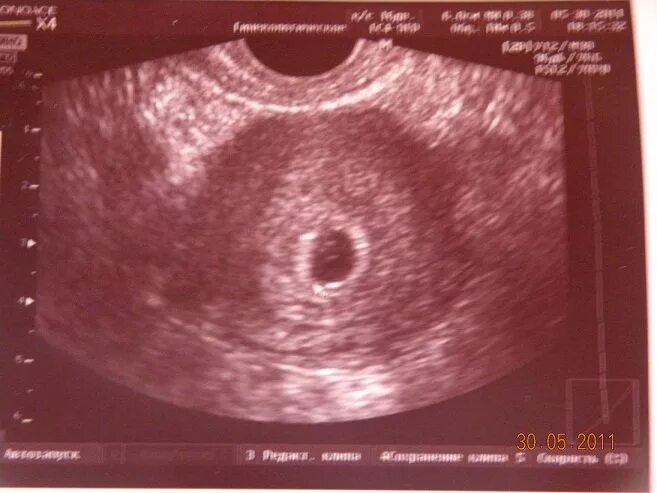

Плодное яйцо размером 3 3